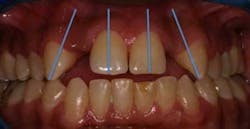

represent the recommended spacing parameter to establish a stable

and esthetic replacement of the maxillary lateral incisor.

The orthodontist and the surgeon must also take into account the space appropriation in the interradicular area as well. The minimum spacing between the roots is generally 5 mm. This amount of space will allow the implant to be surrounded by 0.75 mm and 1.0 mm of bone, which is sufficient to support normal functional loading and ensure good long-term osseointegration. (22) During the space opening aspect of orthodontic care, the orthodontist must make a compensating bend to diverge the roots, especially when canines are initially distal angulated, since the canine root apex inevitably lags behind the crown when distalized. The orthodontist also has to pay particular attention to the skeletal relationship of the patient in these cases because in an Angle Class III tendency type case, the maxilla is narrow and the crowns tend to be tipped labially, which in turn results in adequate space for the restoration but insufficient space at the apex for fixture placement and may necessitate an alternative type of restoration or a shorter implant fixture. (3,6)